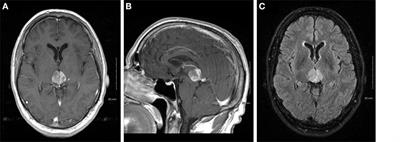

INC实例交流:4年松果体肿瘤病史,德国手术终获完整切除

- 文章标题:松果体区胶质瘤预后好吗?